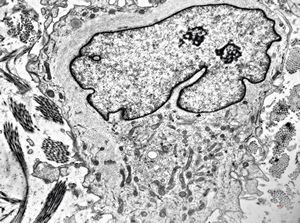

F, 36y. | generalized eruptive histiocytoma - histiocyte